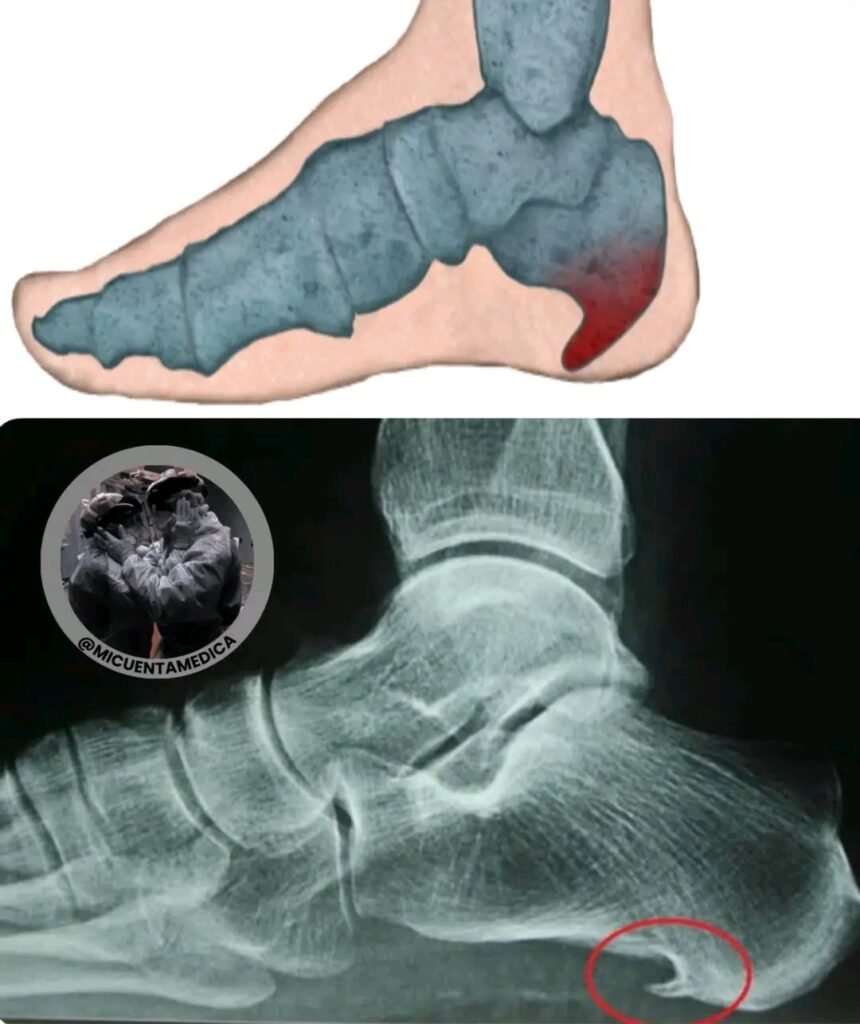

What you see in these images is an anatomical illustration and an X-ray revealing a common but often underestimated problem: the heel spur. It is a bony protrusion, shaped like a spear or spine, that appears on the bottom of the heel bone (calcaneus). It arises when the plantar fascia, an elastic band that supports the arch of the foot, is subjected to constant and repetitive tension.